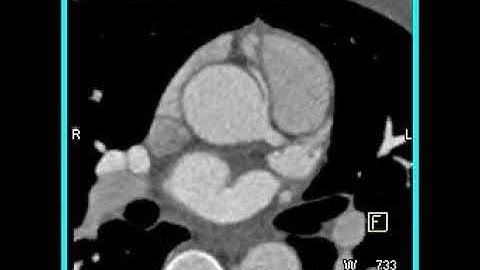

4D endocardium segmentation from a CTA image